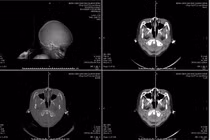

Hình ảnh máu tụ trên phim chụp - Ảnh BVCC

CT sọ não cấp cứu ghi nhận: Tụ máu dưới màng cứng hai bán cầu, bên trái dày tới 18 mm; Xuất huyết dưới nhện rải rác hai bán cầu; Đường giữa lệch 15 mm – dấu hiệu chèn ép não nghiêm trọng; Vỡ xương thái dương phải, xương đá trái, kèm tụ dịch sào bào chũm.

Hình ảnh tổn thương trên phim chụp - Ảnh BVCC